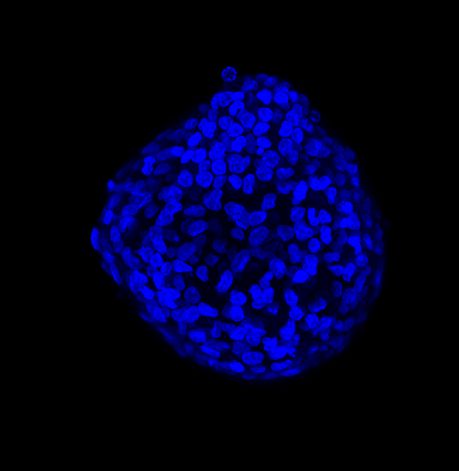

We performed acquisitions with CrestOptics X-Light V3 spinning disk confocal coupled with Prime BSI Camera (Photometrics, 6.5 um pixel size). We compared acquisitions performed with 20x air objective (CFI Plan Apo Lambda, Nikon, 0.7 NA and 1mm WD) and 25x silicone oil objective (CFI Plan Apo Lambda S, Nikon, 1.05 NA and 0.55 mm WD). In Figure A, we show maximum intensity projection (MIP) images obtained from Z stack of 150 um total; in particular, the same spheroid was acquired with 20x air objective and with 25x silicone oil objective. Figure B shows a zoom of the same region of the 3D spheroid acquired with both lenses.

The comparison between the images acquired with the 20x air objective and those with the 25x silicone oil objective (Figure A, B and C) highlights the importance of the lens choice based on the biological application. The transition from 20x to 25x leads to a gain in resolution (based on the greater NA of the 25x compared to the 20x NA), which certainly affects the image quality, and also leads to a reduction in the light refraction. As a matter of fact, immersion oils greatly improve the microscope’s resolving power by replacing the air gap between the lens and the coverslip with a higher refractive index medium, thus allowing to reduce the refraction of light.

In 3D imaging, matching the refractive index of the sample and its immersion medium is crucial for deep tissue observation. Silicone immersion oil is perfect for imaging through thick biological samples; it closely matches the refractive index of cells and of the mounting medium, decreasing spherical aberration and resulting in brighter and higher resolution images compared to those acquired with a common 20x air objective.

Figure B 3D tumor spheroids: Zoom of the same region of the 3D spheroid acquired with the 20x air objective (LEFT) and with the 25x silicone objective (RIGHT). Live cells are labeled with Calcein (green) and dead cells with PI (red). Nuclei are stained with Hoechst (blue). These images were acquired with CrestOptics X-Light V3 spinning disk.